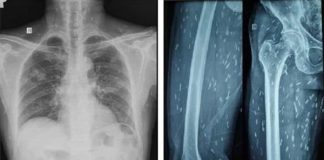

Không có cha mẹ nào không yêu thương con mình, nhưng tình yêu của một số cha mẹ lại vô tình khiến con mắc bệnh UT. Bé gái 8 tuổi tên Lệ Lệ (Trung Quốc) tử vong chỉ sau 30 ngày nằm viện điều trị UT thận. Đây là lời cảnh tỉnh xót xa về [...]